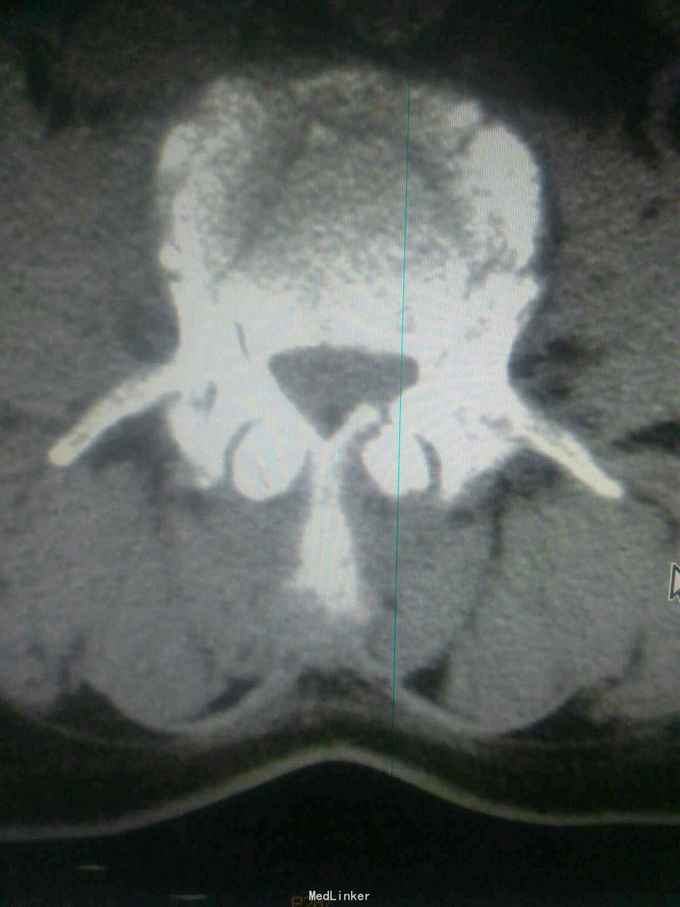

患者因高处坠落致腰痛部疼痛,双下会活动受限9小时入院。患者9小时前从3米高处坠落,腰骶部先着地,即时觉双下肢麻木,不能活动。

查体腰背部压痛,双下肢肌力0级,肌张力减低,会阴区,双下肢痛觉减低,触觉,精细觉正常,腱反射未引出,肛门反射消失,括约肌松弛。

诊断腰1,腰4椎体爆裂性骨折,腰5椎体压缩性骨折,脊髓圆锥损伤双下肢截瘫。患者入院后48小时内行了腰椎后路腰1.4椎体切开复位椎弓根钉内固定,腰1椎板切除,椎管扩大成形,横突间植骨融合术。